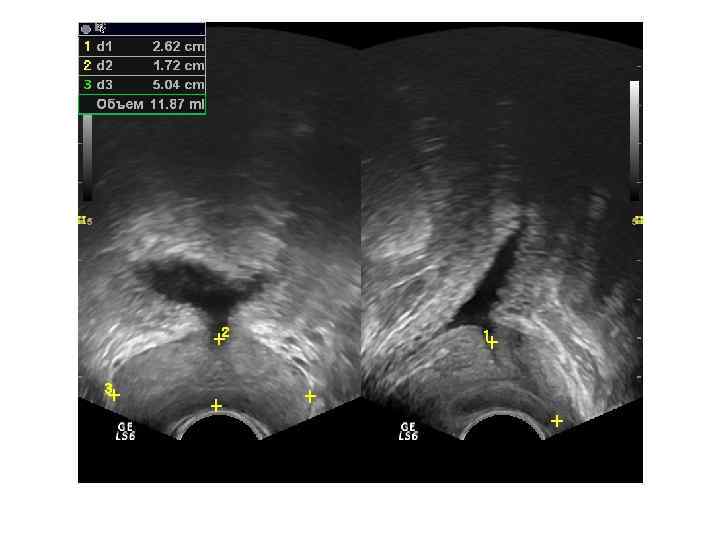

При ТРУЗИ объем простаты может быть определен с помощью нескольких методов: 1. Объем =А х В х С х 0, 52 (рис. 6. 5 А), где А — продольный размер, В — переднезадний размер, С — поперечный размер. Поперечный размер железы определяется при поперечном сканировании в ее средней части, переднезадний и продольный размеры — при сагиттальном сканировании 2. Объем = С 2 х В х 0, 52 где В — передне-задний размер, С — поперечный размер. 3. Объем = С 3 х 0, 52 где С — поперечный размер.

Нормальные размеры простаты